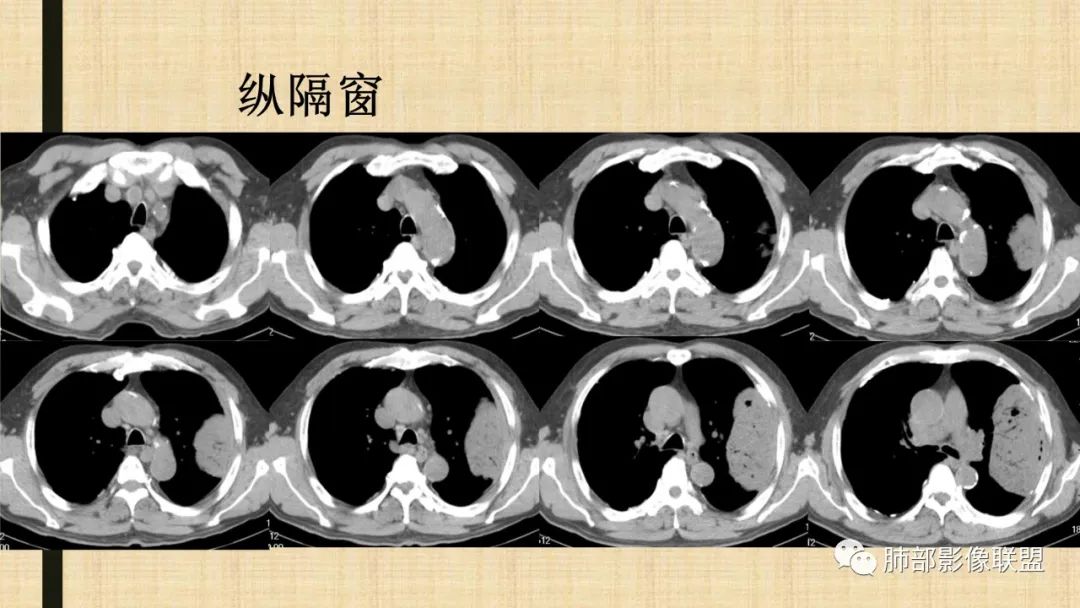

左肺上叶大肿块,膨胀性生长,边界清,密度较低,见部分坏死区,强化弱,肿块见支气管充气V扩张征,分布僵直,枯树枝特点,另一个重要特点血管造影征,淋巴瘤,肿块长轴与胸膜平行,与隐球菌鉴别,隐球荚膜抗原检查,明确诊断经皮肺穿刺。另胸膜钙化(问诊既往有无患胸膜炎病史)。

老年男性,糖尿病病史,消瘦、乏力三个月,影像表现左肺上叶胸膜下团块,有一定张力,内部疏松,可见支气管影及坏死区,增强病灶边缘环形强化,内部未见强化,考虑炎性肉芽肿病变,隐球?奴卡?放线菌?鉴别淋巴瘤。

左肺上叶胸膜下肿块,宽基底与胸膜相连,跨叶裂,边缘清晰膨隆,其内支气管充气,部分扩张、僵直,无明显强化,血管造影征,考虑淋巴瘤,鉴别腺癌

左肺胸膜下巨大占位,跨叶裂,宽基底与胸膜相连,胸膜钙化,平扫密度较低,强化不明显,可见内部血管显影,支气管充气征和扩张,考虑为恶性,倾向于淋巴瘤

左侧胸腔巨大肿块,跨叶生长,临近胸膜钙化,边缘模糊,可见支气管影,定位肺内,增强后轻度强化,边缘见血管影,考虑淋巴瘤,鉴别肉瘤

左肺上叶胸膜下肿块,膨胀性生长,边界清晰,密度不均部分坏死,未见强化,病灶内支气管迂曲扩张,病灶长轴与胸膜平行,胸膜下脂肪间隙存在,胸膜钙化,考虑放线菌?毛霉?鉴别淋巴瘤

支持淋巴瘤,左上肺大肿块,有分叶,边缘光整,病灶内密度不均,可见支气管扩张征,增强后可见血管影征。周围肺野清晰。

左肺上叶肿块,宽基底与胸膜相连,跨叶裂,边缘清晰膨隆,可见小分叶,其内支气管充气,部分扩张、僵直,呈枯枝征,支气管达边征,增强无明显强化,可见血管造影征,考虑恶性病变,淋巴瘤,鉴别粘液腺癌。

大肿块,边缘光滑,深分叶

近端支气管堵塞、推移为主

部分类似于脐凹征

内部支气管扩张

肺动脉推移为主,边缘部分进入

大肿块、表面光滑但深分叶,肺门侧支气管堵塞

1)部位:周围型或中央型软组织肿块,以周围型为多见,且肿瘤多位于肺上叶。如本例:该肿瘤位于左肺上叶。

2)大小及形态:由于本病恶性程度高,早期症状不明显,发现时肿块均较大。如本例病变巨大。

3)肿块边界和边缘:多较清楚,呈圆形、类圆形,且由于肿块生长速度不均匀,可见分叶,毛刺少见。有报道肿块周围毛玻璃影是多形性癌特征表现。

4)密度:肿块平扫为软组织密度,由于体积较大,内部常见大片状坏死,可出现不规则厚壁空洞或坏死内多发无壁小空洞,坏死多不均匀:坏死灶内可见如柳絮样的斑片样强化灶,坏死边缘与非坏死区分界不清本例坏死较明显,密度不均匀。